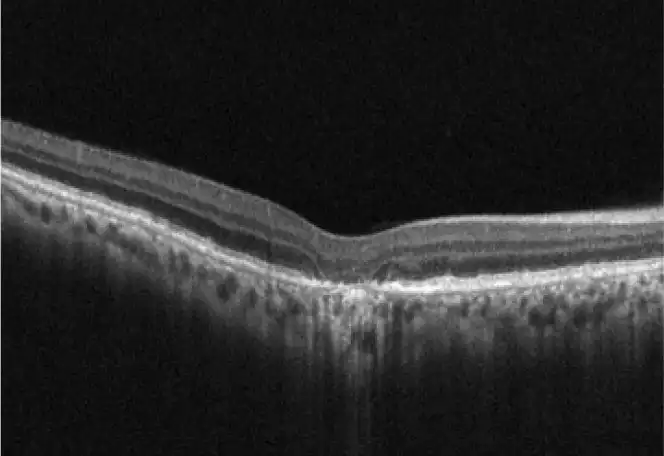

Neovascular AMD

- In clinical trials, use of IZERVAY was associated with increased rates of neovascular (wet) AMD or choroidal neovascularization (7% when administered monthly and 4% in the sham group) by Month 12. Over 24 months, the rate of neovascular (wet) AMD or choroidal neovascularization in the GATHER2 trial was 12% in the IZERVAY group and 9% in the sham group. Patients receiving IZERVAY should be monitored for signs of neovascular AMD.

IZERVAY™ (avacincaptad pegol intravitreal solution) is indicated for the treatment of geographic atrophy (GA) secondary to age-related macular degeneration (AMD)